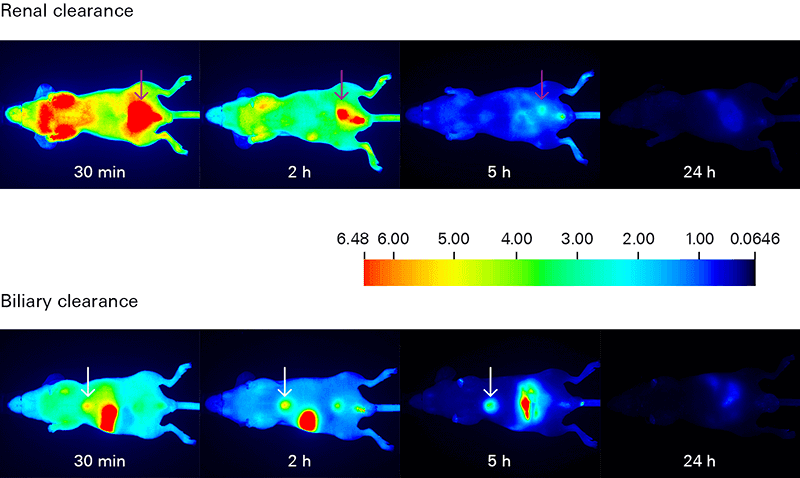

Biodistribution and clearance assessments track the movement of your dye-labeled therapeutic in order to understand its uptake, localization, distribution, and elimination within the animal.

Biodistribution and clearance studies can identify regions and time of specific and non-specific retention of your therapeutic in organs and tissue.

- In vivo biodistribution analysis tracks the localization of your dye-labeled therapeutic and reveals if it is being delivered to your intended target, as well as its elimination route. Non-specific interactions of your therapeutic are very important and should not be overlooked.

- In vivo clearance studies monitor elimination of your dye-labeled therapeutic over time. Understanding clearance is important for optimizing both imaging time and dose, as well as to identify any specific or non-specific retention, which may impact results.

Assessing Biodistribution and Clearance with Near-Infrared Fluorescence

Deep light penetration and minimal autofluorescence from animal tissues make NIR detection ideal for tracking biodistribution and clearance with high sensitivity. Low background yields excellent signal-to-noise ratios for monitoring your dye-labeled therapeutic in vivo and ex vivo.

The Pearl Trilogy Small Animal Imaging System can perform rapid time-lapse in vivo imaging without the need to manually adjust camera settings between scans. For ex vivo analysis, the Organ Tray Base and disposable organ trays provide a non-heated, flat surface for imaging on the Pearl Trilogy system. IRDye Infrared Dyes IRDye 800CW and IRDye 680RD provide excellent performance for in vivo and ex vivo biodistribution and clearance imaging.